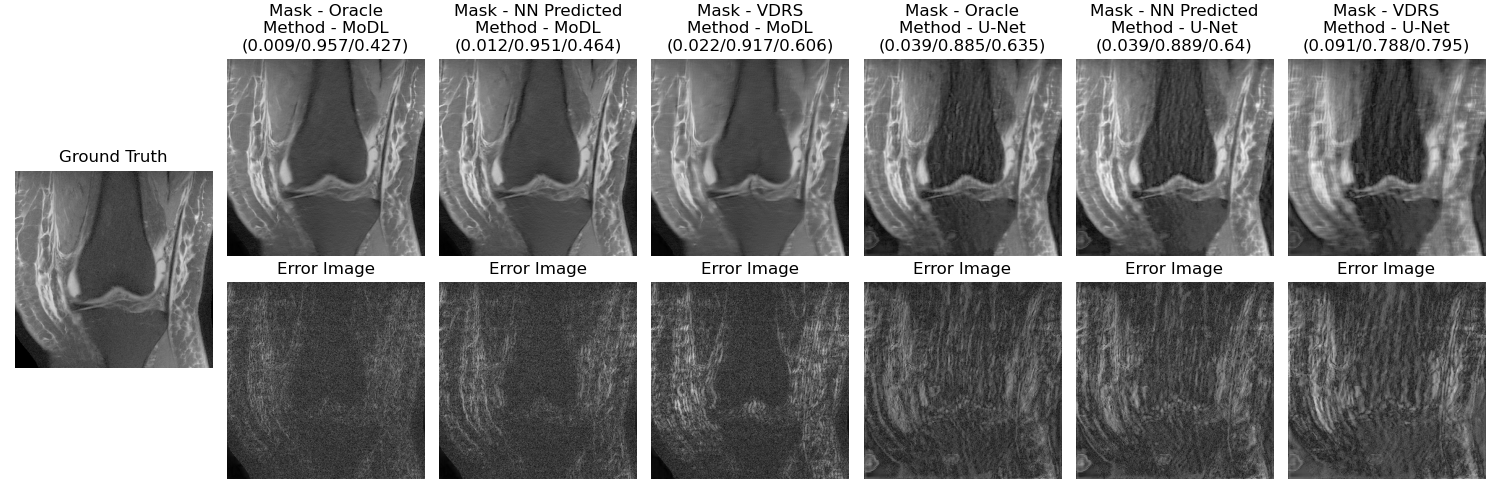

Refer to caption

Fig. 4: Reconstructed and (magnitude) error images for different combinations of masks and reconstructors. Reconstruction metrics shown are (NMSE/SSIM/HFEN)

1 shows the average NMSE, SSIM, and HFEN values over the test cases for different combinations of reconstructors and masks. Figure 4 shows reconstructed images for these combinations of different reconstructors and masks along with the error images for two different scans in the testing set.

Our results indicate better test-time reconstruction quality using an oracle (optimized directly using ICD for the test scan assuming known full k-space) and nearest neighbor sampling mask as compared to the conventional variable density random sampling (VDRS) mask in terms of NMSE, SSIM, and HFEN metrics, and visual quality (Figure 4). The test-time reconstructors used were the trained U-Net and MoDL networks.